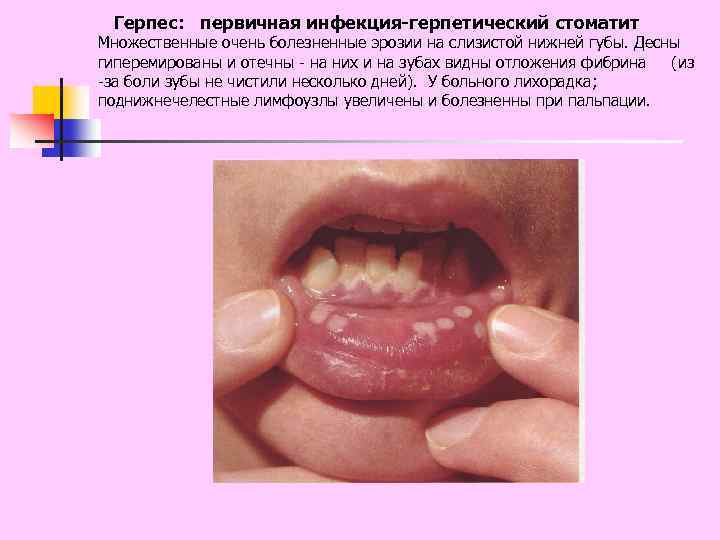

Герпес: первичная инфекция-герпетический стоматит Множественные очень болезненные эрозии на слизистой нижней губы. Десны гиперемированы и отечны - на них и на зубах видны отложения фибрина (из -за боли зубы не чистили несколько дней). У больного лихорадка; поднижнечелестные лимфоузлы увеличены и болезненны при пальпации.

Герпес: первичная инфекция-герпетический стоматит Множественные очень болезненные эрозии на слизистой нижней губы. Десны гиперемированы и отечны - на них и на зубах видны отложения фибрина (из -за боли зубы не чистили несколько дней). У больного лихорадка; поднижнечелестные лимфоузлы увеличены и болезненны при пальпации.